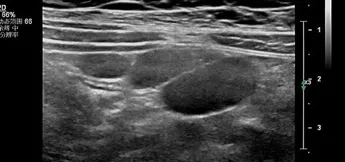

超声作为评估淋巴结最便捷、最直观的检查,能够快速评估淋巴结的形态、结构和血流特征。

淋巴结作为外周免疫系统的核心,由皮质、髓质和包膜3部分组成,广泛分布于颈部、腋窝、腹股沟等淋巴回流区域。根据解剖位置,可分为易触及的浅表淋巴结和难触及的深部淋巴结。儿童淋巴结大小的评估应综合年龄、解剖部位等进行个体化判断。当颈部淋巴结长径>20mm或短径>10mm时;腋窝淋巴结短径>8mm;滑车上淋巴结>5mm;肠系膜区域淋巴结长径>15mm或短径≥8mm或同一超声切面显示有3个或更多聚集时,即可诊断。